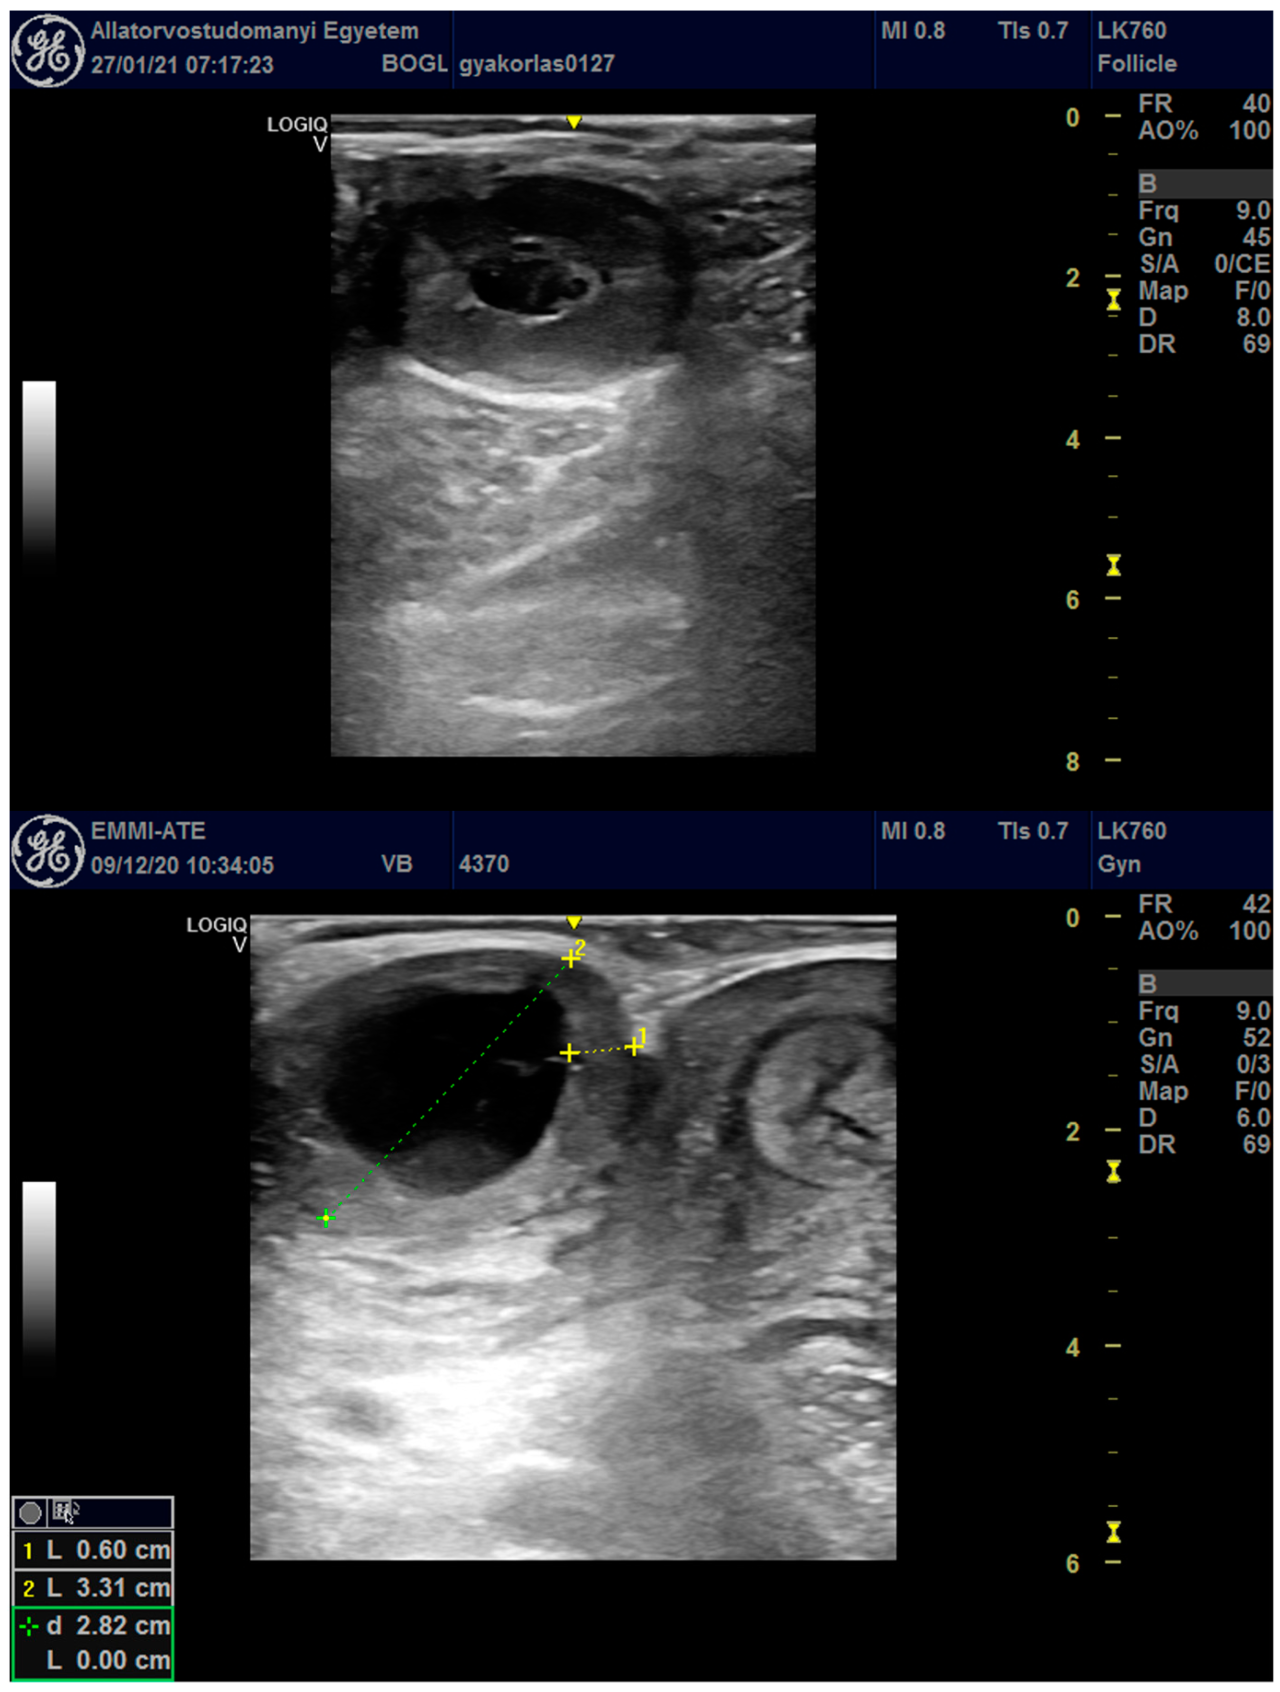

图中显示了一个腔状黄体 (上图) 和一个具有黄素化囊壁和中心大腔的黄素化卵泡囊肿 (下图)。

在全部检查中,91.1%为紧凑黄体,8.9%为空腔黄体。妊娠率在两组间差异极大:紧凑黄体组的妊娠率为43.4% (900/2124),而空腔黄体组妊娠率仅为3.7% (8/216)。统计分析显示,与紧凑黄体相比,空腔黄体的存在使奶牛空怀的几率增加了21倍。此外,8.0%的检查中发现卵巢囊肿,囊肿的存在使奶牛受孕几率大幅降低 (妊娠率仅1.1%),并使空腔黄体的出现几率降低9倍。研究还发现,初产牛的妊娠几率是经产牛的1.9倍;季节对空腔黄体的出现无显著影响,但夏季 (6-8月) 其诊断率略高;产奶量不受黄体类型或季节影响,但经产牛及配种次数少的牛产奶量更高。